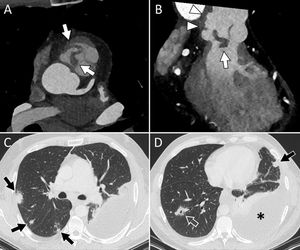

La figura 2 muestra distintos ejemplos del papel de la TC en el diagnóstico de la EID.

Varón de 47 años, ex-ADVP, que ingresa por fiebre y bacteriemia por Staphylococcus aureus. Las imágenes en planos axial (A) y coronal oblicuo (B) confirman la presencia de vegetaciones de gran tamaño sobre la válvula pulmonar nativa (flechas blancas), así como aumento de partes blandas perivalvular sugestivo de flemón/absceso e irregularidad con saculación de la raíz de la pulmonar compatible con pseudoaneurisma (B, cabezas de flecha). Se identificaron múltiples lesiones nodulares pulmonares bilaterales (flechas negras), alguna de ellas cavitada (D, flecha vacía), compatibles con embolias pulmonares, asociadas a derrame pleural izquierdo (D, asterisco).